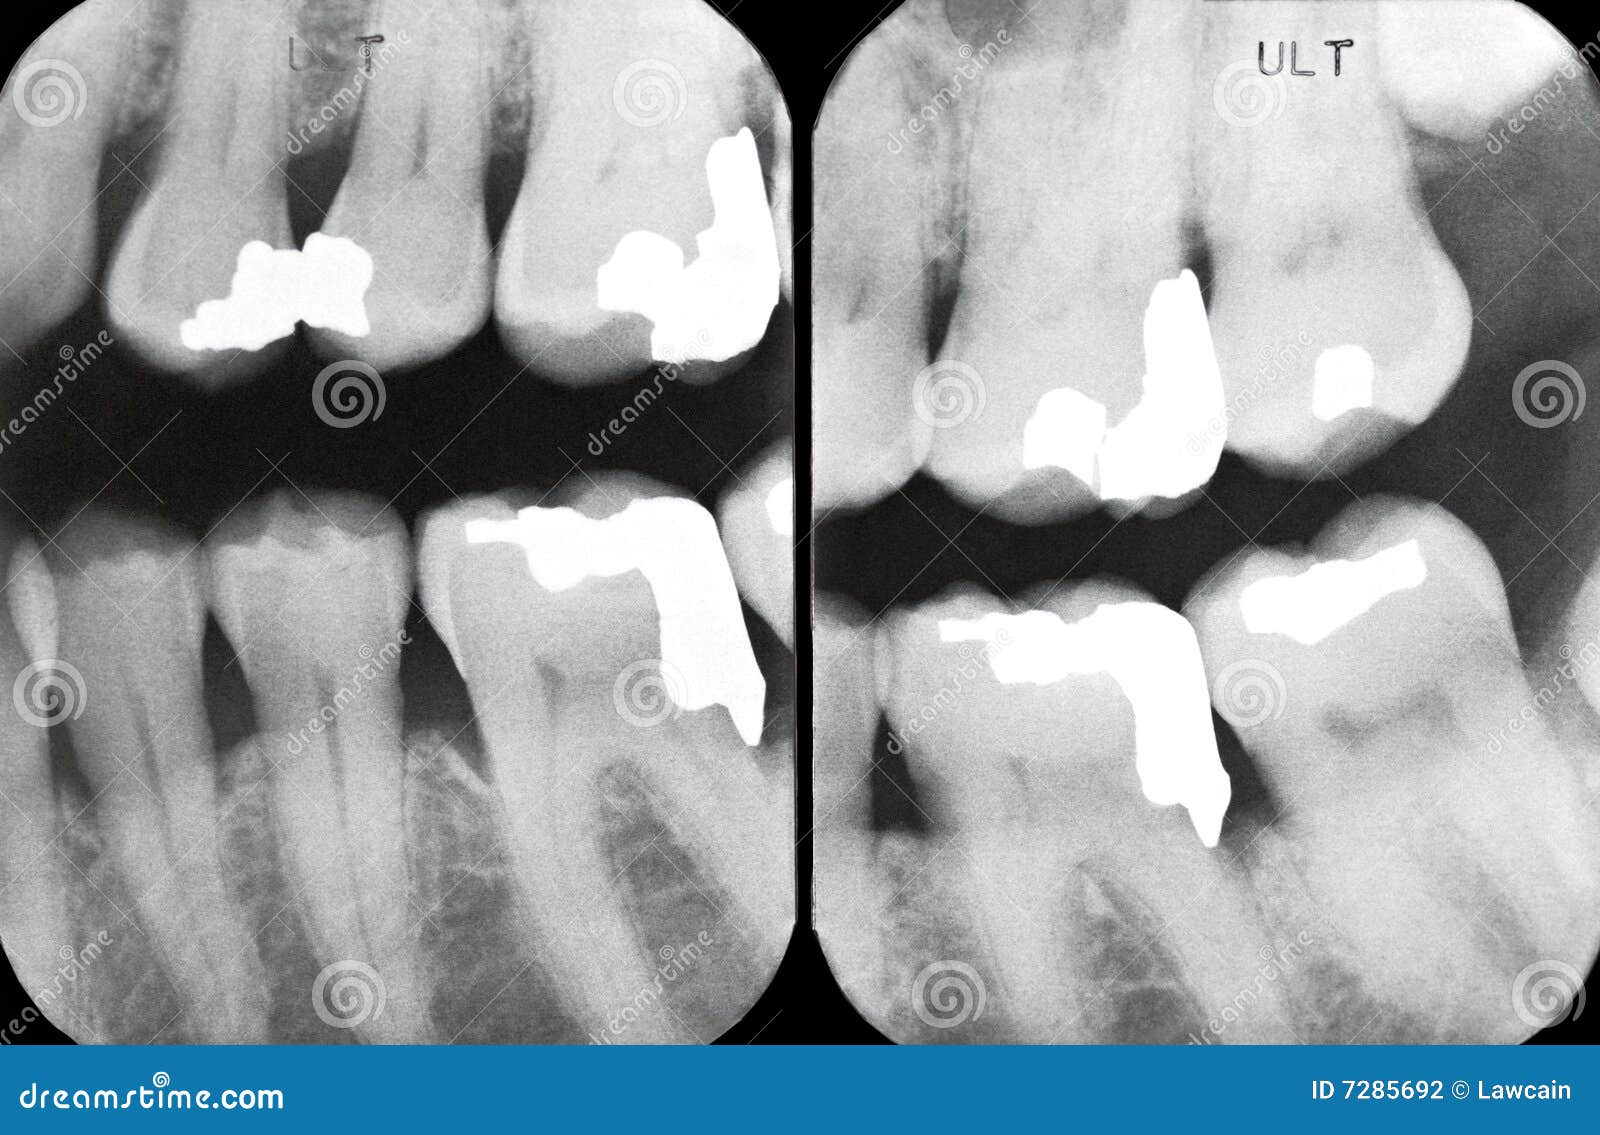

From www.dreamstime.com

Right Periodontal Xrays stock photo. Image of crowns 7285692 X Ray Periodontal Disease They can be used to assess bone loss and the pattern of loss as well as in the. Radiographs are an integral component of a periodontal assessment for those with clinical evidence of periodontal destruction. Periapical radiographs are considered the gold standard for periodontal assessment as they provide extensive information about the extent of bone. Radiographs are commonly used in. X Ray Periodontal Disease.